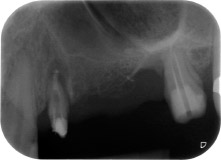

apikale Parodontalläsion an Zahn 24

Abb. 1: Bei einer 58-jährigen Patientin zeigt die Röntgenaufnahme vor der OP eine apikale Parodontalläsion an Zahn 24 und einen horizontalen Knochenabbau im zweiten Quadranten.

Eine 58-jährige Patientin, die auch eine gute Freundin und ärztliche Kollegin ist, beschwerte sich über Schmerzen und erhöhte Beweglichkeit ihres Brückenpfeilers 24. Es lag auch eine parodontale Entzündung vor, mit Taschentiefen von 7 mm mesiobukkal und mehr als 12 mm distal und einer Furkationsbeteiligung dritten Grades. Darüber hinaus zeigte die Röntgenaufnahme eine großflächige apikale Aufhellung am endodontisch (alio loco) vorbehandelten Zahn 24 (Abb. 1).

An der bukkalen Wurzel fehlte der gesamte vestibuläre und distale Knochen. Das Attachment beschränkte sich weitgehend auf die palatinale Wurzel, was die anfängliche schlechte Prognose unterstreicht. Auch Zahn 27 wies ein verringertes horizontales Attachment (vgl. Abb. 12) und eine kleine apikale Aufhellung (Abb. 1) auf, allerdings ohne klinische Symptome.